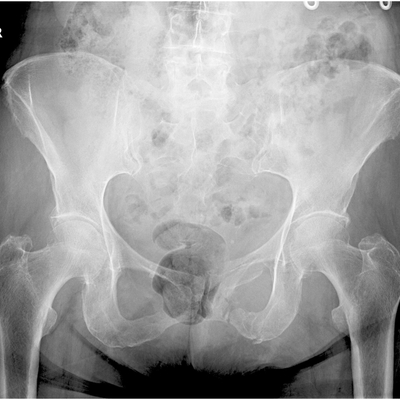

Click on an image below to view more info.